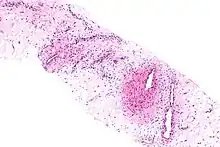

| Micrograph of an aggressive angiomyxoma. Core biopsy. H&E stain. | |

- Vascular appearance of tumor[7]

- Hypocellular mesenchymal lesion

- Spindled and stellate cells with an ill-defined cytoplasm

- Cells loosely scattered in a myxoid stroma

- No evidence of nuclear atypia and mitosis

- Numerous, thin-to-thick wall vessels of different sizes

- Myxoid, hypocellular background

- Bland cytological appearance of spindle cells